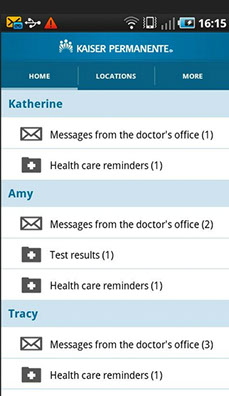

USAA ~ Safeway ~ Limited Brands ~ Macy's ~ Sears ~ Emporium ~ Nokia ~ Motorola ~ Samsung ~ LG ~ BlackBerry ~ HTC ~ Wal-Mart Stores ~ CVS ~ Best Buy ~ Rite Aid ~ Nike ~ GAP ~ J. C. Penney ~ Chevron ~ General Electric ~ AT&T ~ Hewlett-Packard ~ Bank of America Corp. ~ Citigroup ~ Berkshire Hathaway ~ International Business Machines ~ McKesson ~ Kaiser Permanente ~ Kaiser Hospitals ~ U.C.S.F ~ Stanford University School of Medicine/Medical Center ~ Sutter Healthcare ~ California Pacific Medical Center ~ San Francisco General Hospital And Medical Center ~ San Francisco VA Medical Center ~ U.S. Department of Transportation ~ U.S. Department of Homeland Security ~ Exar ~ Boeing ~ AIS ~ Siemens ~ Kaiser People Solutions ~ Cardinal Health ~ Procter & Gamble ~ UnitedHealth Group ~ Kroger ~ Marathon Oil ~ Costco Wholesale ~ Home Depot ~ Target ~ Johnson & Johnson ~ Morgan Stanley ~ State Farm Insurance ~ Dell ~ Boeing ~ Microsoft ~ Walgreen ~ United Technologies ~ Dow Chemical ~ MetLife ~ Wells Fargo ~ United Parcel Service ~ Caterpillar ~ Lowe's ~ Sears Holdings ~ Cisco Systems ~ Johnson Controls ~ FedEx ~ Intel ~ Sysco ~ Comcast ~ Coca-Cola ~ American Express ~ Aetna ~ Motorola ~ Allstate ~ Prudential Financial ~ Tyson Foods ~ Staples ~ Delta Air Lines ~ City and County of Sacramento ~ City and County of San Francisco ~ City and County Oakland ~ San Jose International Airport ~ JFK International Airport